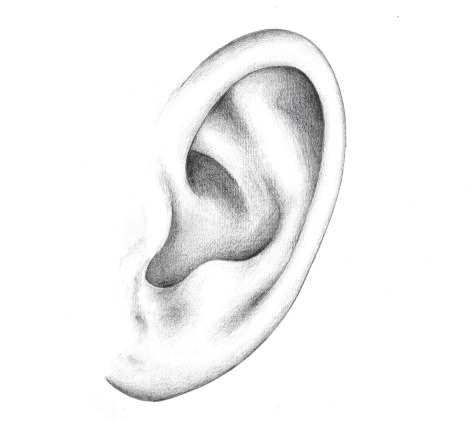

EPITHESE AURICULAIRE

Une épithèse auriculaire est une prothèse spécifique utilisée pour remplacer une oreille externe perdue ou endommagée. Elle est principalement utilisée dans le cadre de la reconstruction auriculaire chez des patients ayant subi une perte partielle ou totale de l'oreille externe.